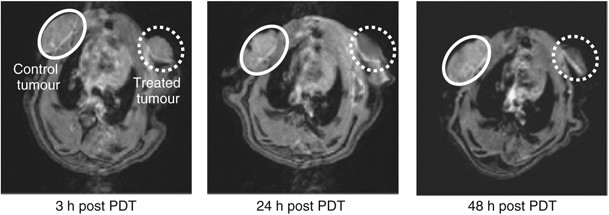

Figure 5

MRI approach to assessing vascular-targeting effect in vivo. The MRI of control 13762 MAT B III rat tumour (white circle) and PDT-treated tumour (0.8 mg kg−1 ADPM06+150 J cm−2 light) (dashed white circle) at ∼3, 24, and 48 h post-treatment with a Gd-DTPA injection, illustrating the change in tumour perfusion.